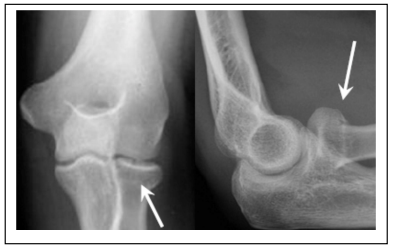

You have a very small break in the radial head or neck – one of the bones in your elbow.